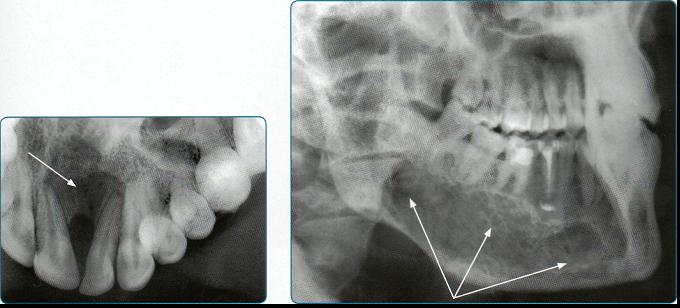

Нижнечелюстной абсцесс